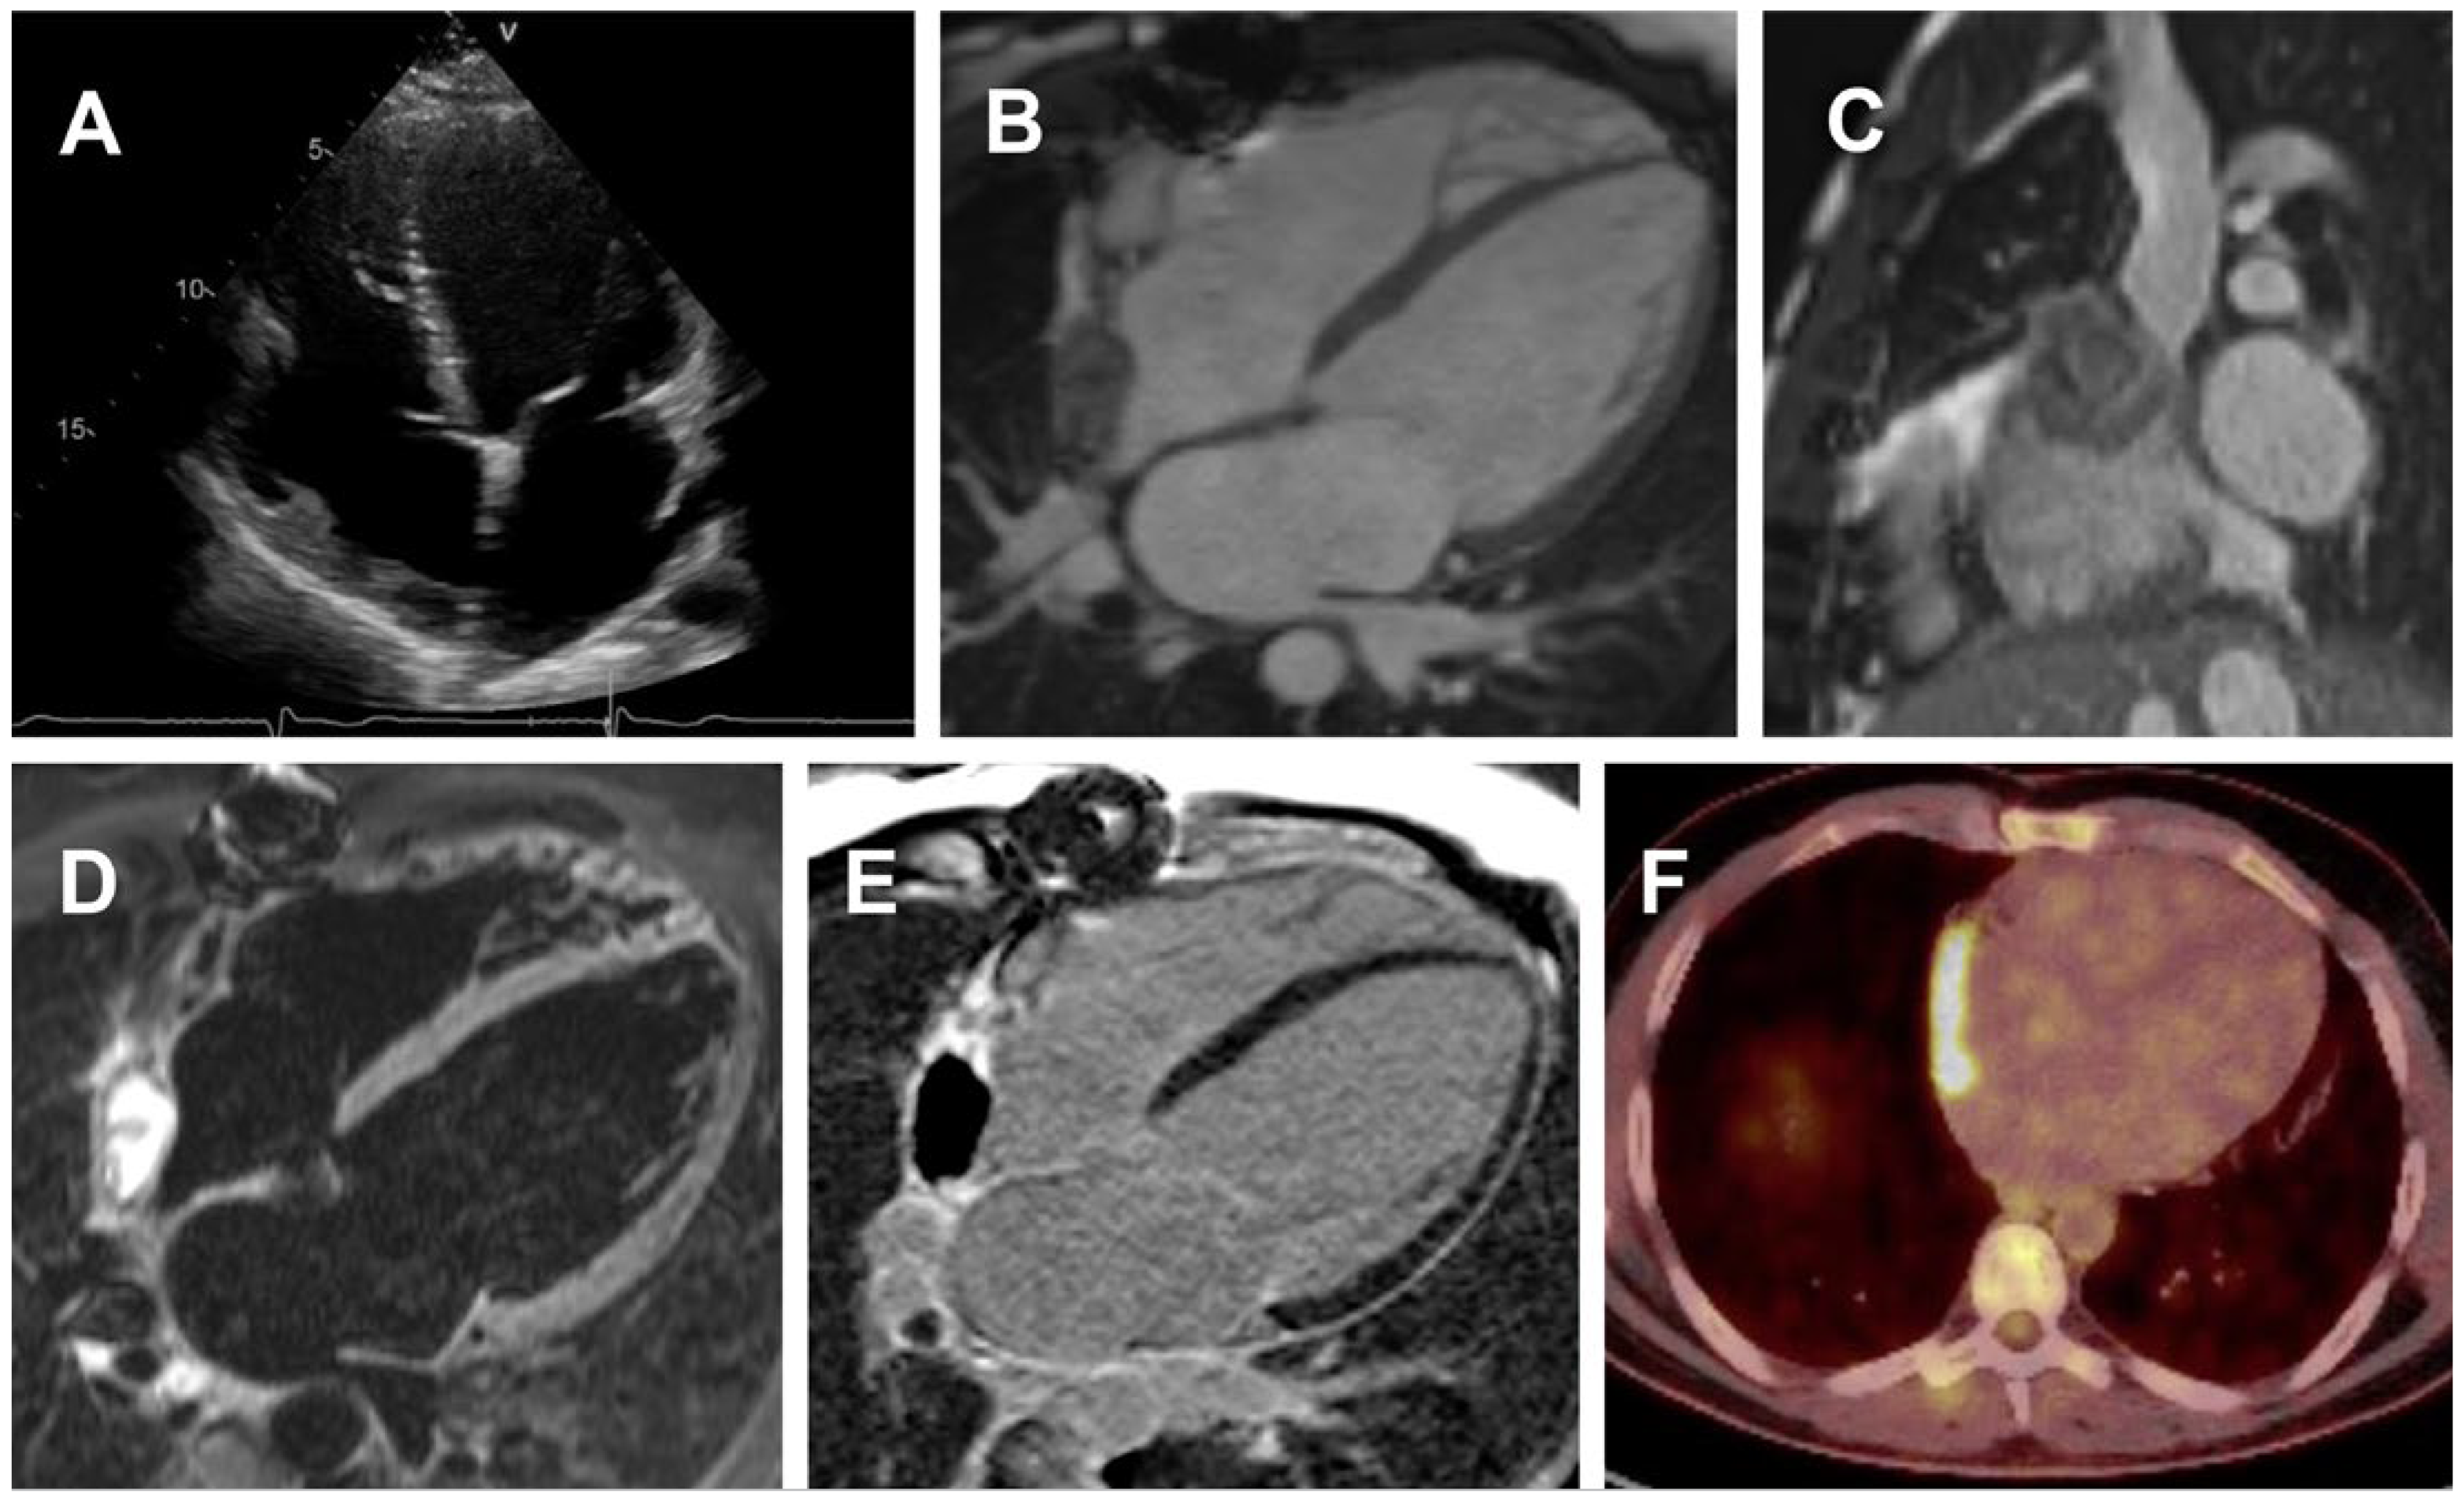

Unfortunately, transthoracic echocardiography 6 months after tumour resection again showed a thickened RA wall near the entrance of the SVC. Repeated CMR confirmed a new 36 × 9 × 41 mm mass with a central core without contrast uptake and a 10 mm thick irregular rim with late enhancement, suspicious of a local relapse of the angiosarcoma (size of the cystic area 28 × 17 × 31 mm). Results of a repeated PET-CT scan also raised suspicion of a local early relapse 7 months after initial in toto resection, without any signs of extended disease. Because of the patient›s young age, we aimed for maximal treatment and redo surgery for an otherwise infaust prognosis. In order to prevent tumour-associated acute cardiac deterioration and to maximise treatment response, neoadjuvant radiotherapy (25 × 2 Gy, 50 Gy GD) was started with concomitant chemotherapy with paclitaxel (seven cycles) (Figure 2A–F). Surgical exploration was performed a couple of weeks after the end of radiation therapy.

Figure 2. Echocardiography, CMR and PET images 6 months after tumor resection suggestive for a local relapse. (A) transthoracic echocardiography showing new a thickened right atrial wall, (BE) repeated CMR demonstrating again a right atrial cystic mass near the entrance of the superior vena cava with irregular contrast medium uptake and a large cystic or necrotic central area, (F) PET-CT revealed abnormal high uptake in this area suggestive for a tumor relapse.